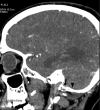

Objective The posterior condylar canals (PCCs), posterior condylar veins (PCVs), occipital foramen (OF), and occipital emissary vein (OEV) are potential anatomical landmarks for surgical approaches through the lateral foramen magnum. We performed the study to make morphometric and radiological analyses of the various emissary foramens and vein in the posterior cranial fossa. Methods Morphometric study were performed on 95 dry occipital bones and radiological analyses on computed tomography (CT) angiography images of 150 patients. The number of OFs on both sides was recorded and PCC length and mean diameters of the internal and external orifices of PCC were measured for bony specimens. Prevalence of PCV and PCV size was investigated using CT angiography. Results Mean PCC length was higher in the left side (9.85 ± 2.5). Mean diameter of the internal orifice and the external orifice diameter were almost the same. The majority of PCCs (75-79.33%) had 2 to 5 mm diameter; only 4 to 9.2% were small in size (< 2 mm). In CT angiography, PCV was not identified in 23 (15.33%) patients. PCVs were located bilaterally in 105 (70%) and unilaterally in 22 (20.5%) patients. Only 11.3% of PCVs were large in size (> 5 mm), 80% of PCVs were medium sized (2-5 mm), and 8.6% were small sized (< 2 mm). Conclusion Normal values of OF, PCC, PCV, and OEV could serve as a future reference for the understanding of the physiology of craniocervical venous drainage, which is necessary to avoid surgical complications and can also serve as a guide to surgical interventions for pathologies of the posterior cranial fossa, such as tumors and injuries.